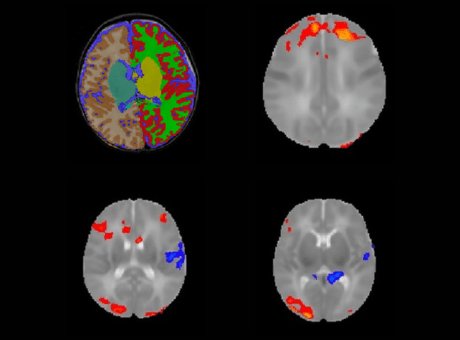

Imaging the fetal brain is challenging as the fetus moves unpredictably during image acquisition resulting in motion degraded images. The lab has created a workflow to create high resolution images from these motion degraded lower resolution images. Additionally, the lab uses these high resolution fetal brain MR images to quantify regional brain volumes, as well as performs placental imaging and quantitative segmentation.

Neonatal brain MRI processing

The lab has expertise in obtaining high quality brain MRI in neonates and young infants without the use of anesthesia using the feed and swaddle technique. Multimodal neonatal and infant brain MR imaging – anatomic, diffusion and BOLD (blood oxygen level dependent) resting state functional MRI are analyzed to understand developmental and functional alterations in the neonatal and infant brain in various conditions. More recently, the lab has investigated infant brain alterations in the setting of prenatal substance exposure.